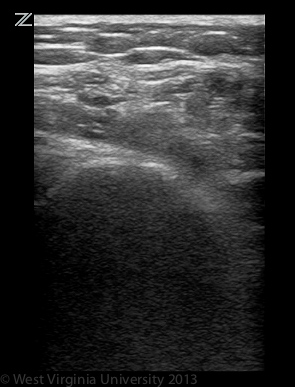

Long Axis Infraspinatus Tendon

The infraspinatus and teres minor muscles share a common tendon that courses over the posterior surface of the humeral head.